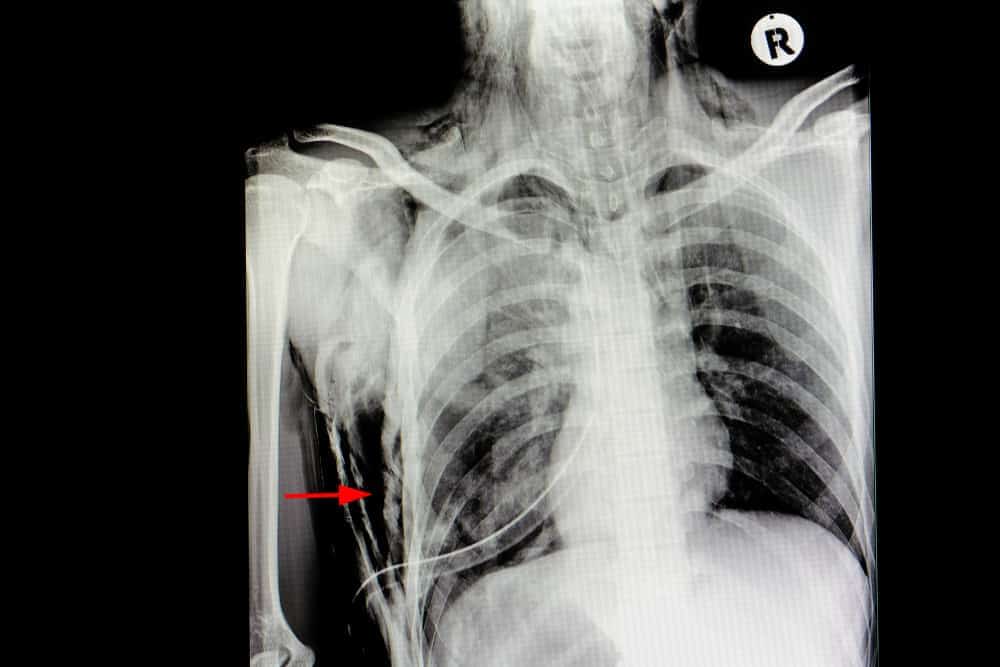

Ang subcutaneous emphysema ay isang kondisyong nangyayari kapag ang hangin ay tumagos sa mga tissue sa ilalim ng balat at sa malalambot na tissues (subcutaneous na layer ng balat). Ito ay pinakakaraniwang nakaaapekto sa malalambot na tissues sa wall ng dibdib o leeg, bagama’t maaari itong makaapekto sa iba pang mga bahagi ng katawan.

• Pneumothorax (pagkasira sa baga na maaaring mangyari kasabay ng bali sa rib)

Ang X-ray imaging at computed tomography (CT) scan ay ilan sa karaniwang tests na makatutulong sa pagsusuri ng prevalence ng subcutaneous emphysema.